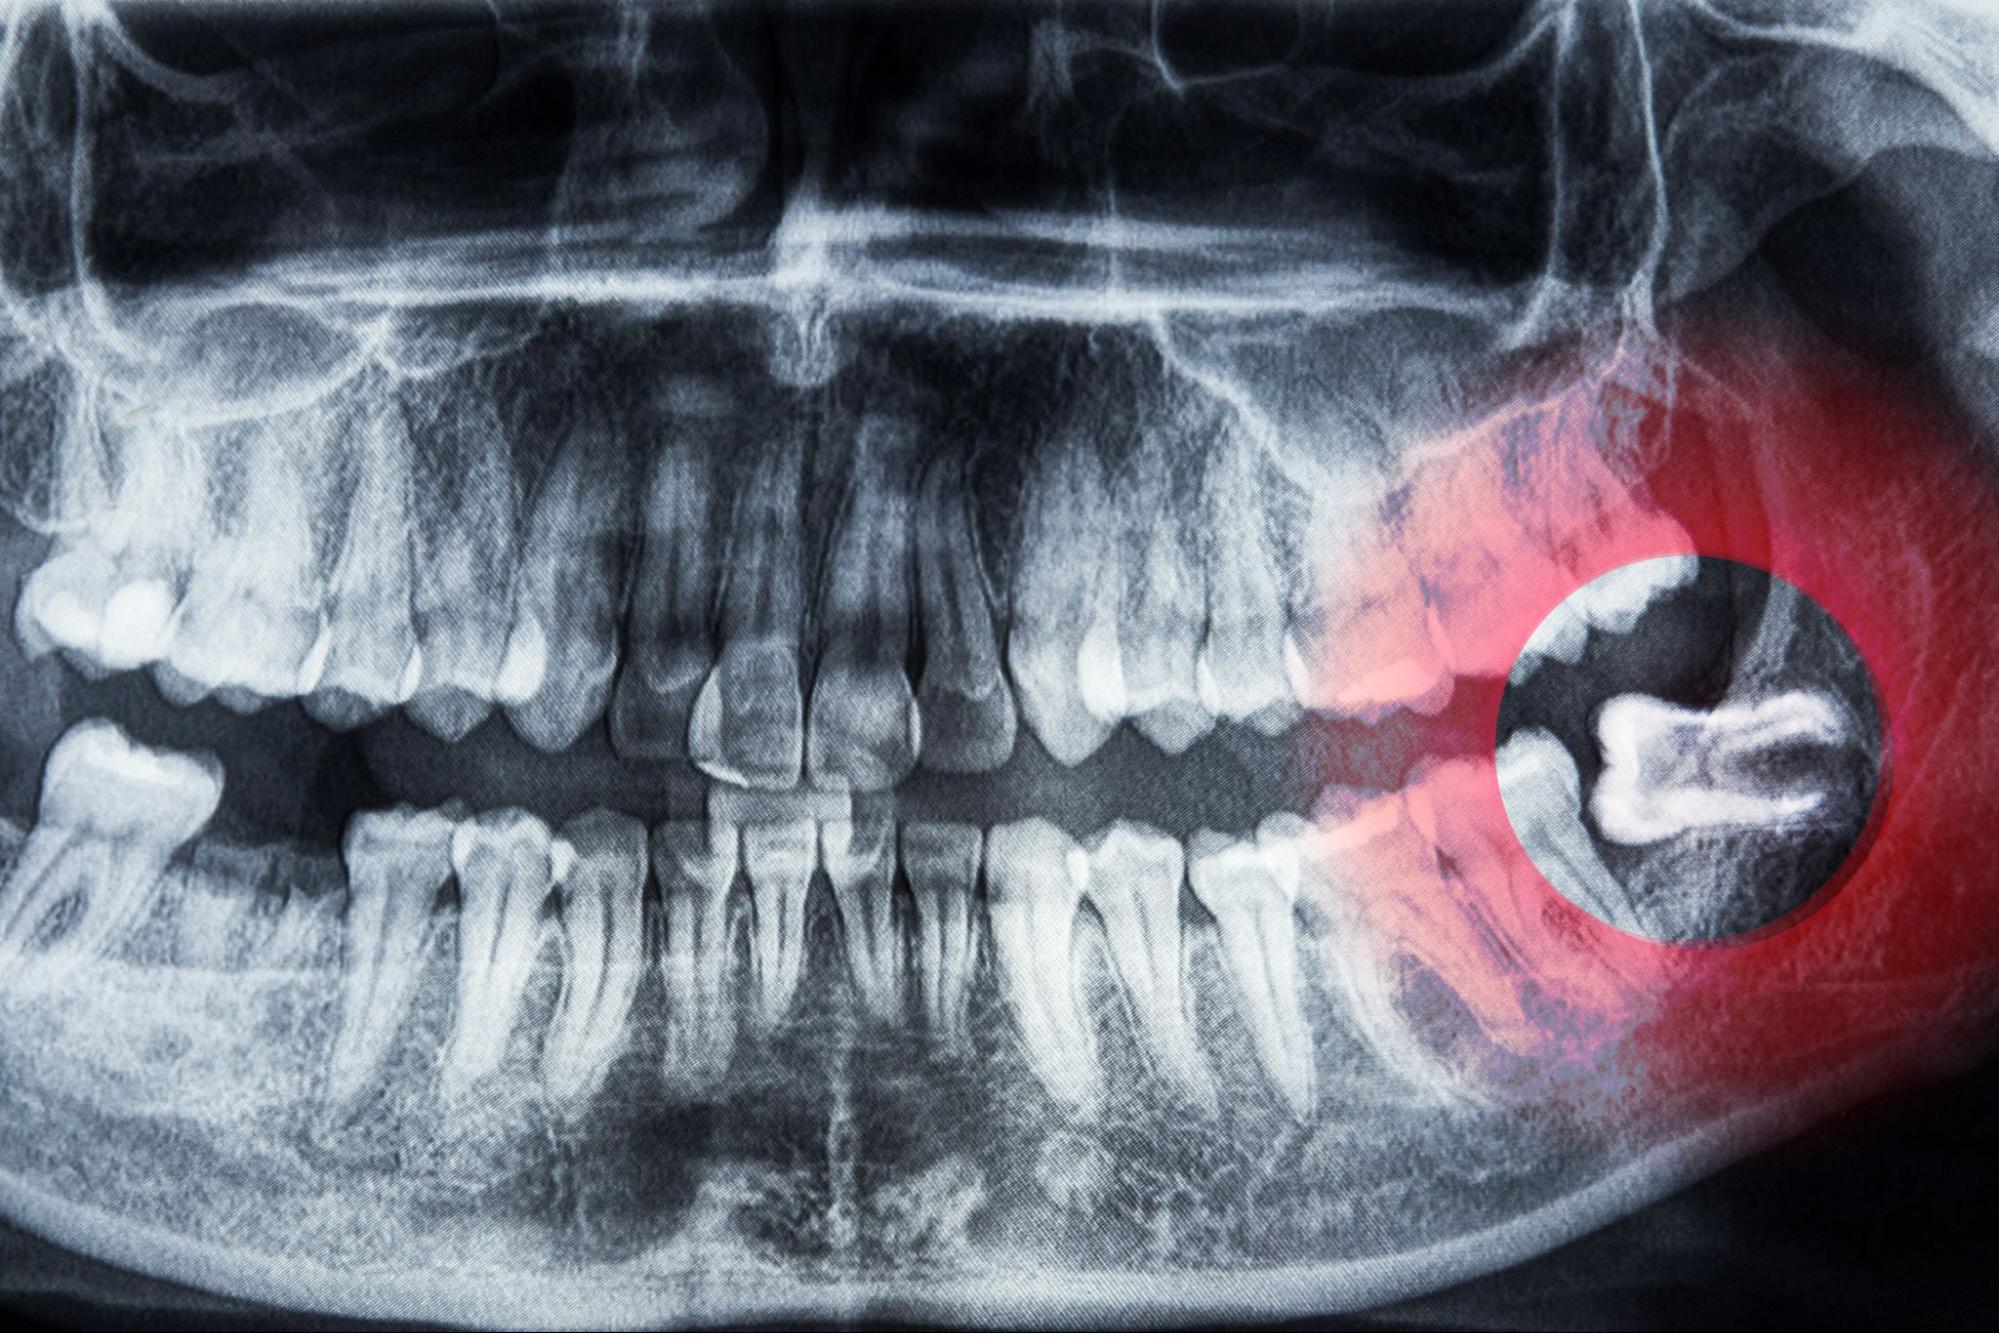

Wisdom teeth often erupt in the late teens or early twenties and may not have enough room to emerge properly. Impacted or partially erupted wisdom teeth can lead to:

We provide evaluation and wisdom tooth extractions when necessary, ensuring you understand your treatment options and recovery process.